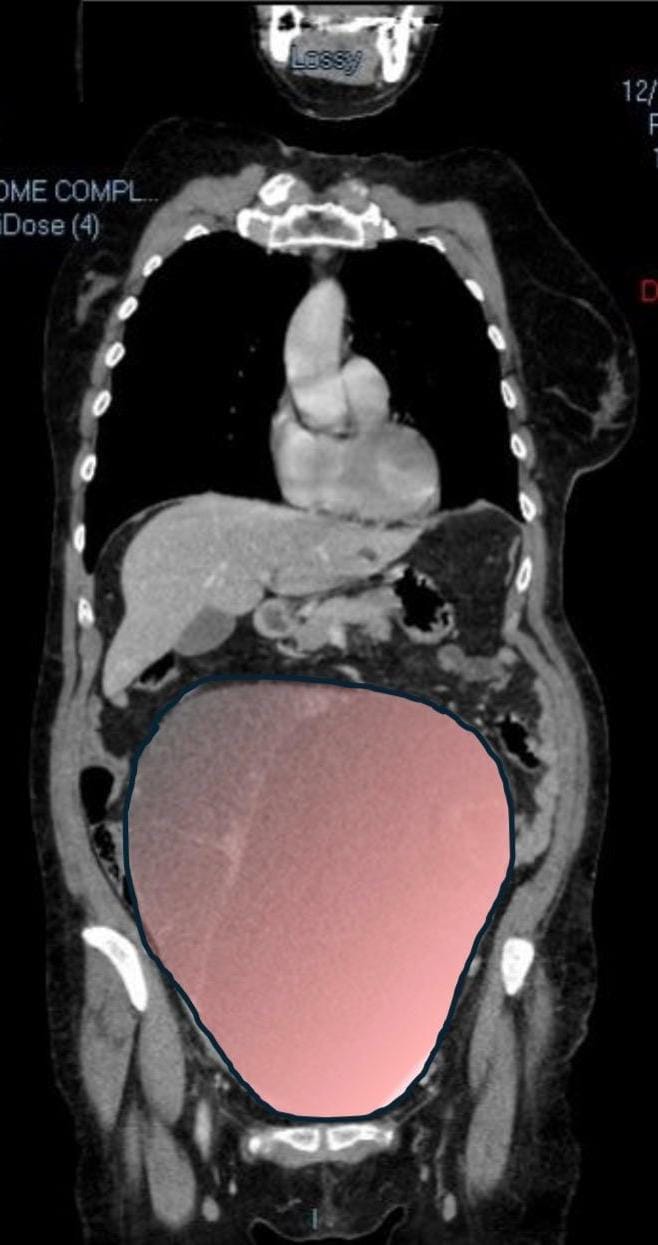

Per mesi la gigantesca cisti ovarica, con un diametro di circa 28 centimetri, è rimasta nascosta, senza dare segnali evidenti. La paziente non si era accorta di nulla. L’allarme è scattato quando la massa, associata alla presenza di una seconda neoplasia intestinale, ha iniziato a comprimere il colon, provocando sintomi acuti ed improvvisi fino ad una grave difficoltà intestinale non più ignorabile.

Durante l’intervento emerge tutta la gravità della situazione. La gigantesca neoplasia ovarica viene asportata: pesa circa 6 chilogrammi, con un volume paragonabile a quello di una gravidanza gemellare a termine. Ma non è l’unica minaccia. I sintomi più pericolosi sono legati alla sofferenza intestinale, che richiede un intervento immediato e coordinato di più specialisti.